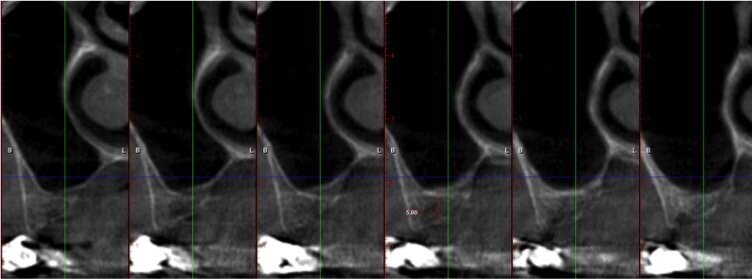

Quando le frese Densah successive avanzano nell’osteotomia, l’osso viene spinto (o densificato) verso l’estremità apicale e comincia a sollevare gradualmente la membrana di Scheneider con l’osso autologo compattato. Utilizzare sempre le frese con movimento di “pompaggio” e abbondante irrigazione, al fine di non surriscaldare l’osso. Per raggiungere una maggiore profondità verticale e il sollevamento graduale della membrana senza perforazioni si consigliano incrementi di 0,5 1,0 mm per fresa, fino ad ottenere la lunghezza e il diametro finale desiderato. Si ricorda che le frese in successione possono raggiungere un sollevamento della membrana di massimo 3 mm. Vista la scarsa qualità e quantità ossea residua del caso in questione, pur usando le frese Densah in modalità di osseodensificazione non si riesce a mantenere una integrità ossea della porzione apicale dei siti osteotomici (Fig. 5). Nei casi di incrementi superiori a 3 mm si può collocare all’interno dell’osteotomia del materiale da innesto, utilizzando l’ultima fresa con velocità di 150-200 giri/min senza irrigazione e in senso antiorario, per compattarlo all’interno dell’osteotomia. In questo caso si posizionano delle membrane di PRF all’interno dei siti osteotomici, così che la membrana di Schneider venga sollevata idrostaticamente con leggere pressioni del PRF (Fig. 6). Finita la fase di preparazione dei siti osteotomici si può procedere all’inserimento implantare a 20 giri/min e 50 Ncm di coppia (Fig. 7). Si esegue a questo punto un innesto di osso eterologo tipo “L-PRF-block”7 per incrementare il volume della zona vestibolare (Fig. 8). Sull’innesto vengono posizionate delle membrane di PRF assottigliate (Fig. 9) e una ulteriore membrana riassorbibile viene posizionata sopra il PRF per assicurare l’immobilità del tutto (Fig. 10). Si procede con l’esecuzione di scarichi di rilascio periostali, per avere un lembo privo di tensioni muscolari (Fig. 11). Infine, viene eseguita una sutura con filo 5 zeri riassorbibile monofilamento (Fig. 12). Nell’immediato post-operatorio viene eseguita alla paziente una CTCB di controllo. Come si può notare dalle sezioni della stessa, la membrana sinusale non risulta perforata, ed è sollevata sugli impianti (Figg 13, 14). Notare la neoformazione ossea apicale agli impianti a 5 mesi dall’intervento (Fig. 15).

Fig. 13 - Sezione panorex post-operatoria: si noti il sollevamento della membrana di Schneider sugli impianti.

Fig. 14 - Sezione cross section post-operatia zona 24.